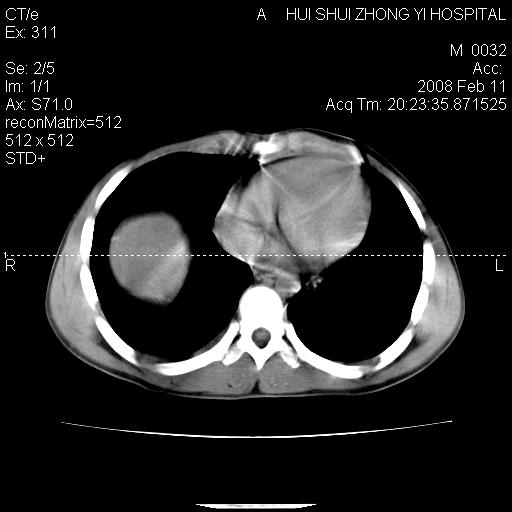

8年前曾在贵洲省人民医院b超诊断为肝内胆管结石。现腹痛剧烈,现发烧、头痛、恶心呕吐县医院b超示胆囊肿大大小159*46mm,囊内见6*5mm强回声光团,胆各总管内径56mm。提示:胆囊结石、急性胆囊炎、胆总管重度扩张。

胆囊结石.急性胆囊炎.重度胆管扩张.右侧胸腔少量积液,建议ct增强

考虑先天性胆管囊肿;胆囊增大并结石。右侧胸腔少量积液,建议ct增强。

caroli囊肿并囊内结石。胆囊增大并胆结石。典型!

先天性胆管囊肿,胆囊结石、胆囊增大,右侧少量胸腔积液。